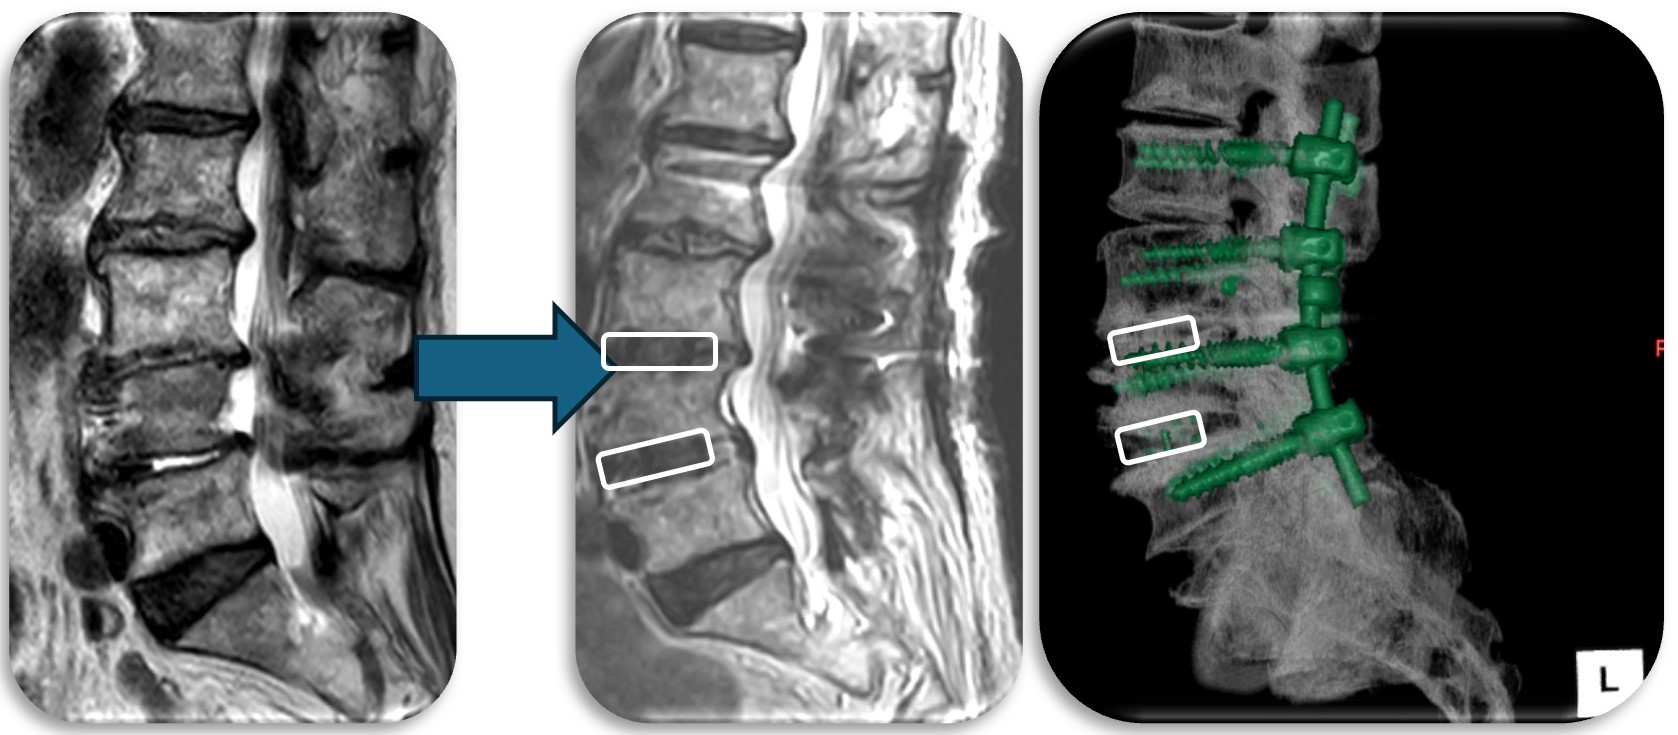

(代表例)

腰部の馬尾神経に発生した神経鞘腫の症例。脊髄腫瘍としては比較的多く割合を占める神経鞘腫は良性腫瘍であり、基本的には全摘出が可能で予後も良好です。この症例も坐骨神経痛と間欠跛行という馬尾障害の症状を呈していましたが、術後は改善し再発も認めておりません。